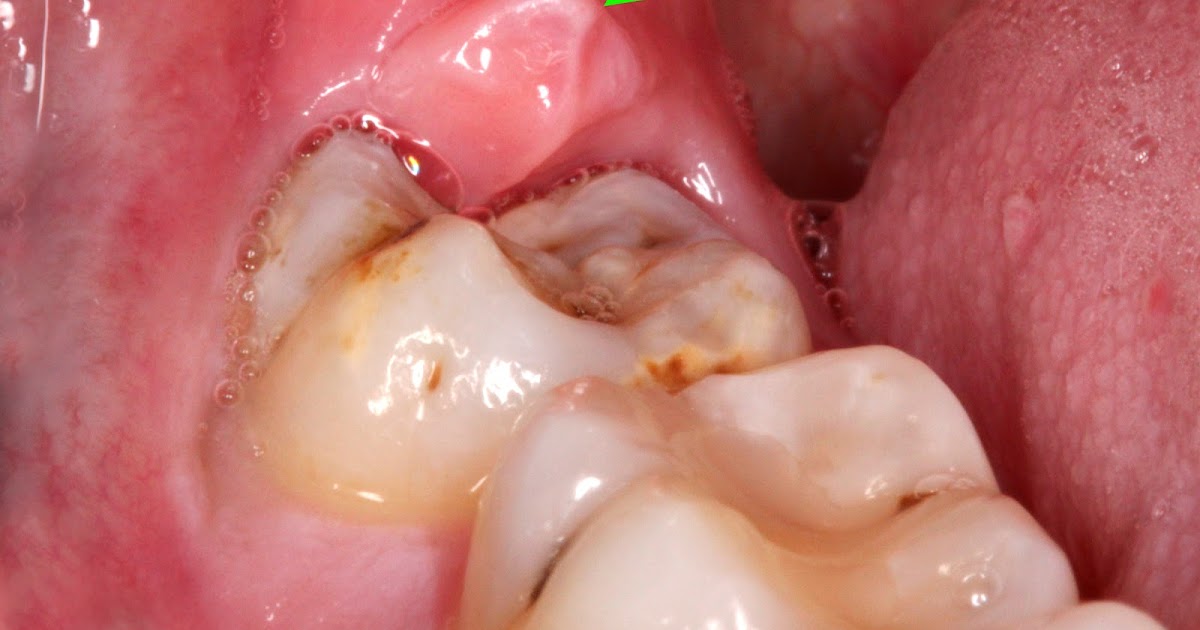

Impacted Wisdom Tooth Due To Which a Gum Hood Was Formed. Inflammation of the Gums Due To an Infection In Gums Wisdom Tooth pericoronitis occurs when the wisdom teeth do not have enough room to erupt through the gums. This can happen when a tooth is still partially. It is most commonly found around the lower wisdom teeth. But when an impacted wisdom tooth becomes infected, damages other teeth or causes. pericoronitis (or operculitis) is a type of gum infection. . Infection In Gums Wisdom Tooth.